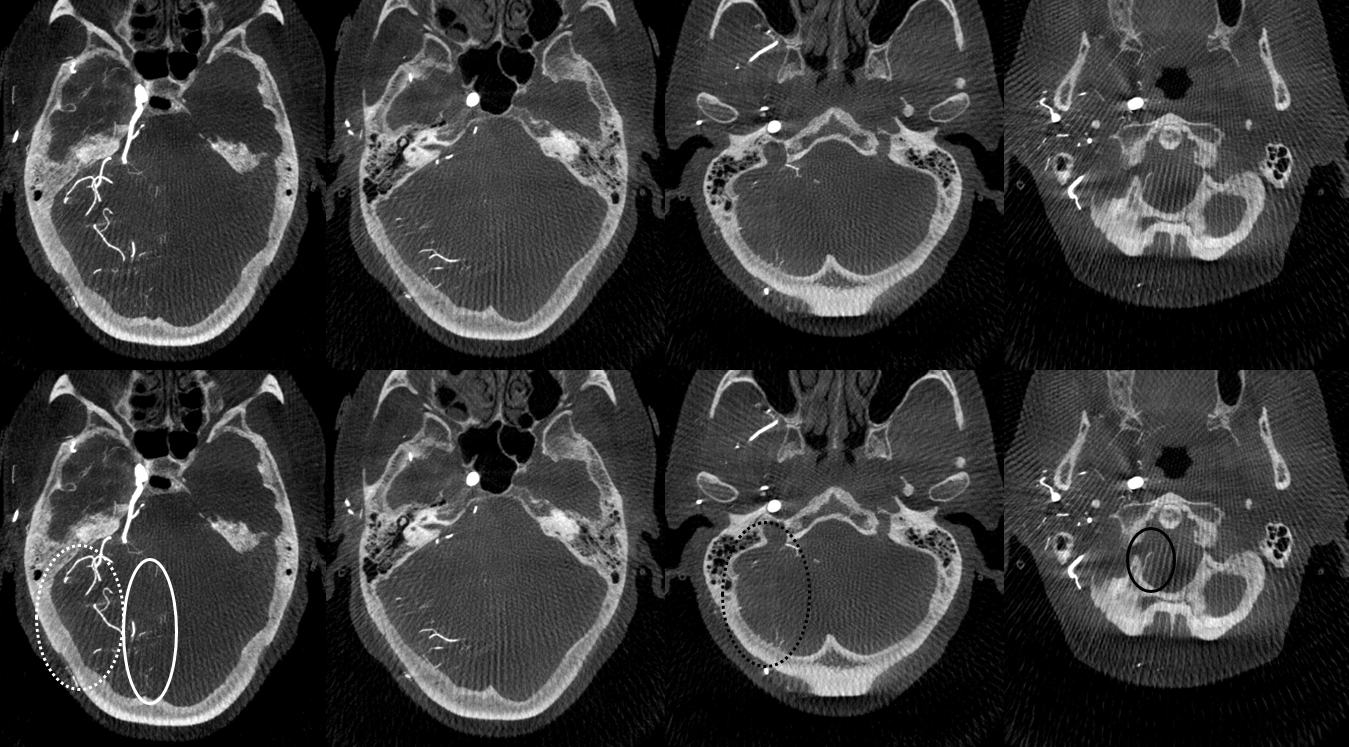

MIP images. Superior vermian territory = white oval; lateral SCA territory = dashed white oval; AICA (minus the labyrinthine branch) = dashed black oval; inferior PICA/down to tonsillar branch = black oval